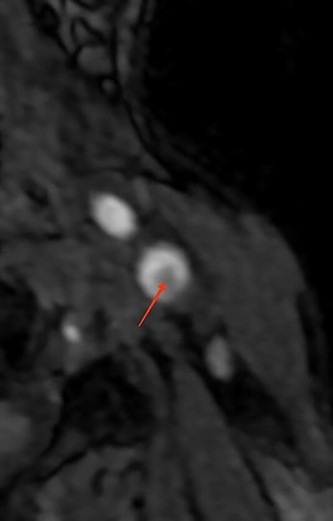

| • Supra-aortic trunks and cerebral arteriography: typical aspect of carotid diaphragm | • Supra-aortic trunks echo Doppler + agioscanner: carotid diaphragm with floating thrombus of the right carotid artery(Fig. 1) | • MRI and supra-aortic trunks angiogram: carotid bulb thrombus (Figs 2 and 3) | • Angioscanner: very suggestive of carotid diaphragm |

MRI reconstruction image of the left carotid bifurcation showing the carotid diaphragm.